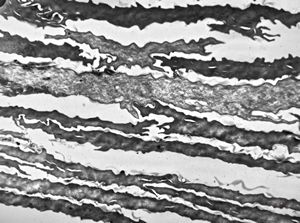

F, 39y. | collagenous and elastin fibers from corium

F, 39y. | collagenous and elastin fibers from corium

F,68y. | collagenous and elastin fibers from corium